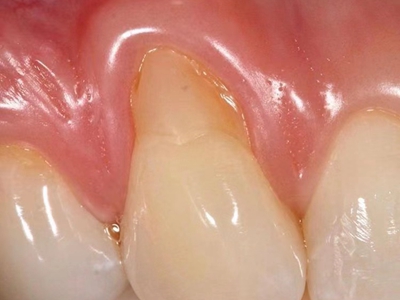

牙龈退缩露出淡黄色牙根图

牙龈退缩患者的牙龈退缩后,淡黄色牙龈明显露出。若进一步发展,易使对应位点的牙槽骨发生骨吸收,可能诱发龋齿、牙龈敏感、菌斑堆积等。